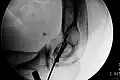

Elastisch stabile intramedulläre Nagelung (ESIN)

Diese Modifikation des Verfahrens mit Bündelnägeln wird heute fast ausschließlich bei Kindern und Jugendlichen mit offenen Wachstumsfugen verwendet. Das Verfahren hat sich aus der Anwendung der Endernägel entwickelt. Im Gegensatz zu den bei Erwachsenen verlassenen intramedullären Drahtnagelungen bewährt sich die ESIN (Synonyme: Prevot-Nagelung, Nancy-Nagelung) bei Patienten im Wachstum aufgrund der besseren Frakturheilung und wegen der einfachen und zuverlässigen Anwendung.

Es handelt sich bei den Implantaten um biegsame elastische Nägel aus Edelstahl oder Titan, die an ihrer Spitze eine Abflachung und eine Abwinkelung tragen, um in der Markhöhle von Röhrenknochen zu gleiten und sich durch die elastische Spannung in der Markhöhle zu verklemmen. Bei geeigneten Brüchen aller großen Röhrenknochen (Oberschenkel, Schienbein, Oberarm, Speiche und Elle) wird durch einen kleinen Hautschnitt in Nähe aber unter Schonung der Wachstumsfuge die Markhöhle des Knochens mit einer Ahle eröffnet. Durch diese Öffnung wird in absteigender oder aufsteigender Richtung ein erster elastischer Nagel eingeführt. Er wird mit drehenden Bewegungen über die Bruchregion geschoben, die unter Röntgensicht korrekt geschlossen oder bei Nicht-Reponierbarkeit offen durch einen Schnitt eingerichtet wird. Die aufgebogene Spitze kann auch als Hilfe bei der Einrichtung (Repositionshilfe) genutzt werden. Unter weiterem Vorschieben verankert sich der Nagel endgültig kurz unterhalb der jeweiligen anderen Wachstumsfuge des Röhrenknochens. Zur ausreichenden Stabilisierung wird mit Ausnahme bei den paarigen Unterarmknochen ein zweiter (oder selten auch ein dritter) Nagel durch einen separaten Zugang in gleicher Verlaufsrichtung eingeführt.

Wenn beide Nägel eingeschlagen sind, werden sie mit einem Bolzenschneider gekürzt, so dass sie unter der Haut verschwinden, aber noch ausreichend lang aus dem Knochen stehen, damit sie wieder zu entfernen sind. Meist wird die Versorgung von beiden Seiten einer Extremität (innen und außen) durchgeführt, es können aber auch beide Nägel z. B. am Oberarm von seitlich absteigend eingeführt werden, wenn auf der Innenseite Gefäße oder Nerven durch die Implantation gefährdet wären. Die ESIN erreicht bei Kindern und Jugendlichen bei geeigneten Brüchen eine gute Übungsstabilität und früh eine Belastungsstabilität. Eine zusätzliche Gipsbehandlung ist nicht notwendig. Die Nägel können durch einen ebenso kleinen Hautschnitt nach wenigen Monaten wieder entfernt werden.

- Fallbeispiele

-

Mit ESIN versorgter schultergelenknaher Oberarmbruch beim Kind. Ausheilungsbild mit deutlich sichtbarem Frakturkallus (Pfeil) -

Komplette Unterarmschaft-fraktur beim Kind mit deutlicher Knickbildung -

Versorgung derselben Fraktur mit je einem Prevot-Nagel (ESIN) in Radius und Ulna